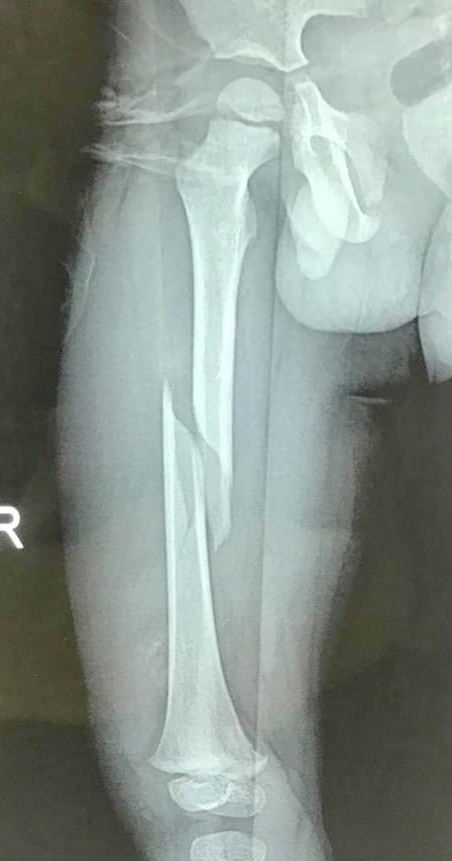

Trao đổi với PV VietTimes, BS. Trần Cửu Long Giang – Trưởng Khoa ngoại Thần kinh - Chấn thương Chỉnh hình, Bệnh viện Hữu Nghị - cho biết: Bệnh nhi nhập viện do tai nạn cột bê tông đè vào chân. Đây là một thương tổn nặng khiến bé bị gãy chéo vát thân xương đùi phải – một xương dài lớn nhất trong cơ thể, gây ra tình trạng mất máu nhiều. Ngoài ra phần mềm cân cơ bao quanh xương còn bị đụng dập nhiều. Mặc dù bé đã được nắn chỉnh bó bột nhưng kết quả không như mong đợi.

Các bác sĩ tại Khoa Ngoại Thần kinh - Chấn thương chỉnh hình, Bệnh viện Hữu Nghị đánh giá đây là trường hợp gãy chéo vát, di lệch nhiều, rất khó năng chỉnh bằng phương pháp bó bột.

Phần xương đùi bị gãy của bệnh nhi. Ảnh: Bệnh viện Hữu Nghị